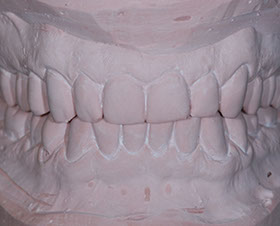

due impronte della bocca da cui si ricaveranno dei modelli in gesso

Nei ragazzi di età superiore (quando la maggior parte dei denti permanenti sono in arcata) e negli adulti, si interviene con trattamenti fissi mirati sia alla risoluzione delle malposizioni dentarie, sia alla correzione degli incongrui rapporti intermascellari in modo da allineare i denti e migliorare l'estetica raggiungendo una buona funzione masticatoria.